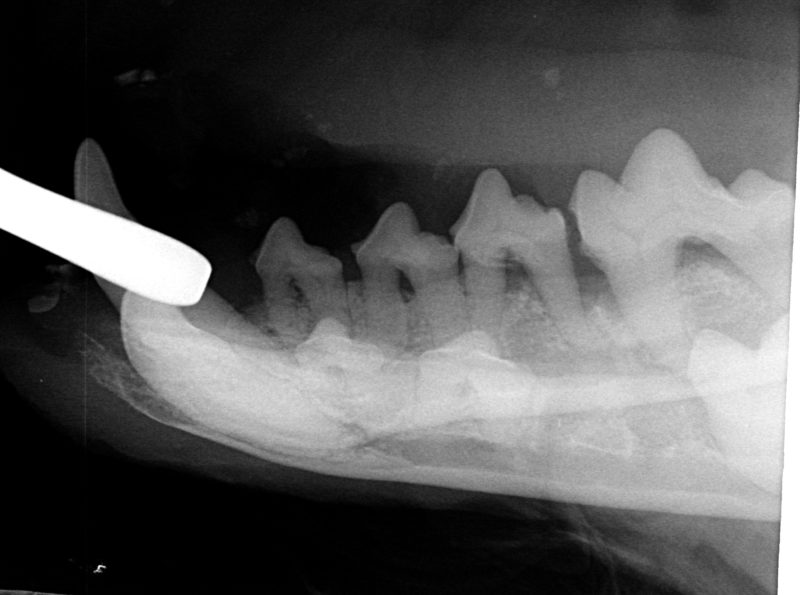

Die Röntgenaufnahme (Bild 4) bewies dann auch, was ich schon aufgrund der typischen Vorgeschichte hatte vermuten müssen: Die Zahnpflegebemühungen im Pudelsalon waren zwar gut gemeint. Für Herkules und sein chronisch entzündetes Zahnfleisch allerdings sehr schmerzhaft. Und vor allem völlig uneffektiv! Während sich die Hundepflegerin mit dem Kratzer an den sichtbaren (oberhalb des Zahnfleisches gelegenen) Zahnbelägen abgemüht hatte, fand der wirklich gefährliche, zahnzerstörerische Krankheitsprozess unsichtbar unterhalb des Zahnfleisches in der Tiefe des Zahnbettes statt! Zu allem Überfluss neigen viele Hunde (vor allem Terrier-Rassen) dazu, dass in solchen chronischen Fällen das Zahnfleisch anschwillt (Zahnfleisch-Hypertrophie) und damit die Taschen am Zahnhals immer tiefer werden. Das mögen die Eiterbakterien!

Die Untersuchung mit der Zahnsonde zeigte dann auch, dass sämtliche Zähne im Maul von Herkules extrem tief und mit Eiter und Gewebsresten, Haaren und Futterresten gefüllt waren. Diese Untersuchung wird zu Beginn einer Sanierungsbehandlung in Kurznarkose durchgeführt. Zuvor werden alle Zähne oberhalb und unterhalb des Zahnfleischrandes mit einem Ultraschall-Scaler gereinigt. Dieses Zahnstein-Entfernungsgerät kennt man vom eigenen Zahnarzt. Mit Ultraschall und reichlich Spülflüssigkeit wird das gesamte Gebiss gereinigt, was man beim Hund ausschließlich in Narkose machen darf, weil die Tiere den Ultraschall viel intensiver wahrnehmen würden als wir Menschen. Nach kompletter Gebissreinigung, Taschensondierung und Befundung der Röntgenaufnahmen kam dann für Herkules die Stunde der Wahrheit: In der Tiefe hatte die chronische Zahnfleischvereiterung zur Zahnlockerung und sogar zu einem weitreichendem Knochenschwund geführt. Auf der Röntgenaufnahme (Bild 5) sieht man deutlich, dass alle zweiwurzligen Backenzähne nicht mehr tief vom Knochen umschlossen werden und sich der Kieferknochen generell zurückgebildet hat. So mussten die wackeligen hinteren Backenzähne alle gezogen werden, ebenso die kleinen Schneidezähnchen. Schade, diesen Zähnen konnte ich nicht mehr helfen, aber Herkules blühte auf, weil er keine Zahnschmerzen mehr hatte und den ganzen Eiter nicht mehr runterschlucken musste. Auch die bereits deutlich veränderten Blutwerte und seine körperliche Leistungsfähigkeit verbesserten sich sehr schnell. „Wir haben wieder einen jungen, agilen Hund“, freute sich Frauchen anlässlich der Nachuntersuchung zwei Wochen später